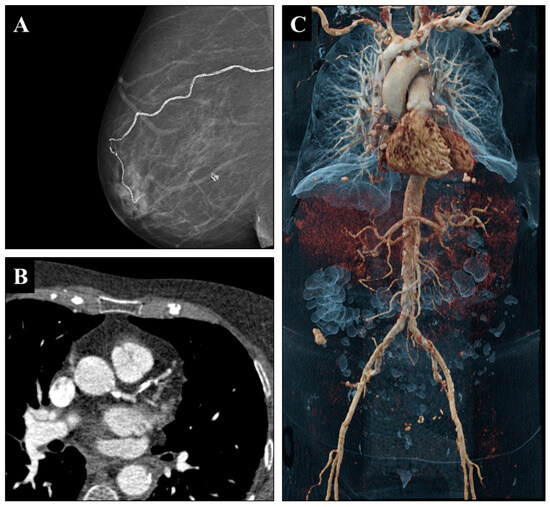

Objective: This study systematically evaluates the association between breast arterial calcifications (BACs) on mammography and systemic vascular calcifications detected by computed tomography (CT) in female lung transplant recipients, representing the first investigation of this relationship in this population. Methods: This retrospective single-center study [...] Read more.

Objective: This study systematically evaluates the association between breast arterial calcifications (BACs) on mammography and systemic vascular calcifications detected by computed tomography (CT) in female lung transplant recipients, representing the first investigation of this relationship in this population. Methods: This retrospective single-center study included 78 female LTX recipients who underwent both digital mammography and thoracoabdominal CT. BACs were graded on a four-point scale. Calcifications in seven arterial territories were visually assessed on CT with a binary scale (“present”, “not present”) and graded on a severity scale of systemic calcifications ranging from no involvement (0) and minor vascular calcification (1–4 vessels) to major vascular calcification (5–10 vessels). Associations between BACs and systemic vascular calcifications were analyzed using correlation, logistic regression, and ROC analysis. Results: BACs were present in 31 of 78 patients (40%). Vascular calcifications were frequent, most often affecting the thoracic aorta (82%), abdominal aorta (76%), and iliac arteries (72–73%). Coronary calcifications were more common in BAC-positive than BAC-negative patients (77% vs. 40%, p = 0.002). BAC grade correlated with the cumulative vascular calcification (ρ = 0.35, p = 0.0017). In ROC analysis, BACs discriminated patients with vascular calcification with fair accuracy (AUC 0.73, 95% CI 0.67–0.79). In multivariable logistic regression adjusted for age, diabetes, chronic kidney disease, and hypertension, BACs remained independently associated with systemic calcification, with an adjusted odds ratio of approximately 2.0 for ≥1 affected vascular territory. Interreader agreement for the 4-level BAC score was excellent with a quadratic-weighted κ of 0.91 and a linear-weighted κ of 0.88. Conclusions: BACs are common in female LTX recipients and independently predict systemic vascular calcifications. Their detection in routine mammography may provide a simple, opportunistic marker to support cardiovascular risk stratification in this high-risk population. Full article